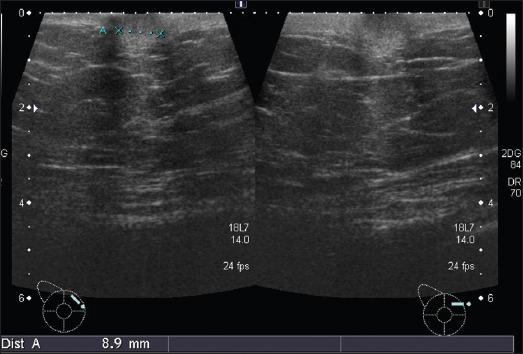

A total of eight cases were identified, out of which seven were females. The most common presentation consisted of the presence of metastatic nodules which were seen in 62.5% (five out of eight) of the patients. Other features consisted of erythematous or plaque-like skin thickening on clinical examination, increased density with indistinct margins seen on a mammogram and diffuse oedematous changes in the skin with small irregular mass or infiltration into subcutaneous tissues were visualised on ultrasound and CT studies.